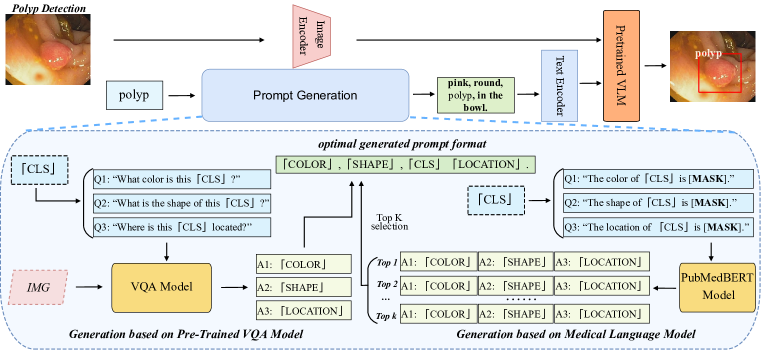

Figure 1 (right) illustrates the overall flow of our MLM-driven auto-prompt generation pipeline. We first ask the model which contains medical domain-specific knowledge to predict the masked token in given cloze sentences we design. The template of the cloze sentences is given as: ‘The [Attr] of an [Object] is [MASK]’, where the ‘Attr’ and ‘Object’ tokens are provided and represent the desired attribute name and category name respectively. This operation could be formulated as:

Image Specific Auto-Prompt Generation Although with the above MLM-driven prompt generation approach, we can successfully generate auto-prompts that are supported by expert-level knowledge, the prompts are still not flexible enough to include image-specific attribute information. Therefore, in this section, we further propose an image specific auto-prompt generation approach by adopting pre-trained visual question answering (VQA) models, e.g., the OFA model (Wang et al., 2022). As demonstrated in Figure 1 (left), we ask the VQA models multiple questions related to the desired attributes iteratively. For example, we can ask the model: ”What color is this wound?”. We expect to receive a proper answer from the VQA model and take that answer as the value for the related attribute. Unlike the MLM-driven approach, we won’t ask for top- answers due to the computation time constraint. This process has to be applied to each image input to generate image-specific prompts, which means the corresponding prompt for each image can vary. Given an image input , the corresponding prompt could be formulated as follows:

The effectiveness of attribution injection and auto-prompts In section 3.2, we discussed that adding attributes could make the models perform better in zero-shot tasks. Here, we demonstrate in Figure 3 (left) an overall pattern of the effect of attribute injection on performance under the zero-shot setting. As shown in the figure, the overall performance increases as more attributes are integrated into the prompts. This is also illustrated in Table 4 on the BCCD dataset, where various attributes and their combinations are shown to improve the results. As this process is rather tedious and time consuming, we need qualified automatic approaches to accelerate the generation process to scale up without sacrificing too much performance. Fortunately, the models with our proposed auto-prompts, especially with the hybrid and MLM-driven approaches, show comparable results to those with manually created prompts and surpass those with default prompts by a landslide. For example, the MLM-driven approach achieves an AP of 24.8% for zero-shot on the DFUC2022 dataset, while the GLIP-T baseline with default prompts only gives 0.1% for the zero-shot performance (Table 2). Figure 4 shows an example of the auto-prompt generation with the hybrid approach.

To automatically generate prompts for unseen concepts, we design various pipelines for obtaining external knowledge from different sources. For the Language Model (LM) based method, as demonstrated in the methodology section, we use PubmedBERT as our knowledge source and use a template to elicit the attributes’ knowledge. For example, if we want to obtain the potential color, shape, and location of polyps from the LM, we will make a template such as “The color of polyps is [Masked]” and ask the language model to predict the “[Masked]” token. Since the BERT-like language model is all pre-trained with the masked token prediction task, the above method can elicit the most likely word for the masked token. Therefore, the LM will give us a probability distribution over all tokens in its vocabulary, and we can take the tokens with top-3 probability as our answers. Furthermore, we use the predicted color as the attribute value for the unseen object to make up our prompts. So, in a nutshell, we first make up a template with the masked token for each attribute, then we use the LM model to do the masked token prediction task to obtain the values. After we collect all the attribute values we need, we then fill these values into our pre-defined prompt template. For example, suppose we receive the words such as “pink”, “round”, and “rectum” for the color, shape, and location attributes of polyps. In that case, we fill the template “Polyp is a [color] and [shape] bump in [location]” with the corresponding words to obtain our prompt: “Polyp is a pink and round bump in rectum.” One can directly use this sentence as the final version to be feeded to the GLIP model. However, because of the implementation detail of the GLIP model which we will not elaborate here, it is better to rearrange the sentence above to a format of a composition of phrases, such as “pink, round, bump, in rectum”. The words before the word “bump” will be treated as a prefix, while the words after the word “bump” will be treated as suffix by the GLIP model. For further detail of this arrangement, please refer to the code of the GLIP model.

The workflow of the image-specific VQA method is quite similar to the pipeline above, except we change the knowledge source from the LM model to the VQA model. And for the VQA model, we don’t ask the model to predict a masked token; we let it answer our pre-defined question for each attribute and collect the answers.

The hybrid approach is simply a combination of the LM-based and VQA-based methods. We use the VQA model to get the shape and color of the unseen objects since these attributes can vary from image to image. We then use the LM model to predict the possible location of the unseen concepts. After all, we combined the attribute values received from both methods to fill into the prompt template.